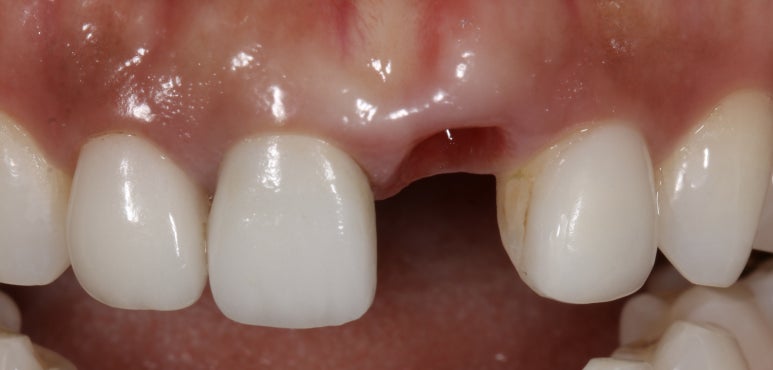

이후에 임플란트와 뼈가 잘 붙게 되면,

수술 4개월 후 - 잇몸 높이가 대칭이 맞아진 것을 볼 수 있습니다

위와 같이 잇몸 주위 조직이 건강하게 치유가 되고 옆 치아와 잇몸 높이 대칭성도 잘 맞게 아문 것을 확인할 수 있답니다.